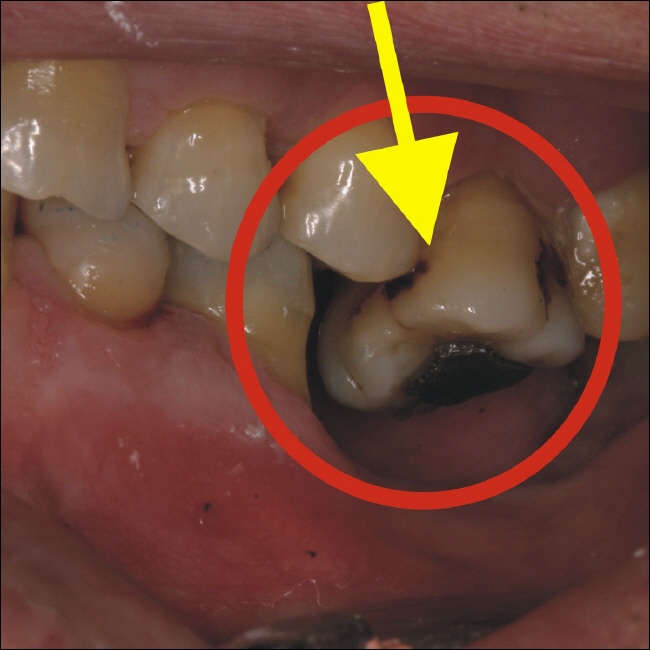

Warten Sie nicht so lange! Das Bild oben läßt es leicht erahnen. Durch den herausgewachsenen Zahn (gelber Pfeil) sind massive Veränderungen im Kausystem enstanden. Bei Kau- bzw. Mahlbewegungen können die Zähne nicht mehr auf ihren dafür vorgesehenen Flächen gleiten, da der herausgewachsene Zahn das verhindert.